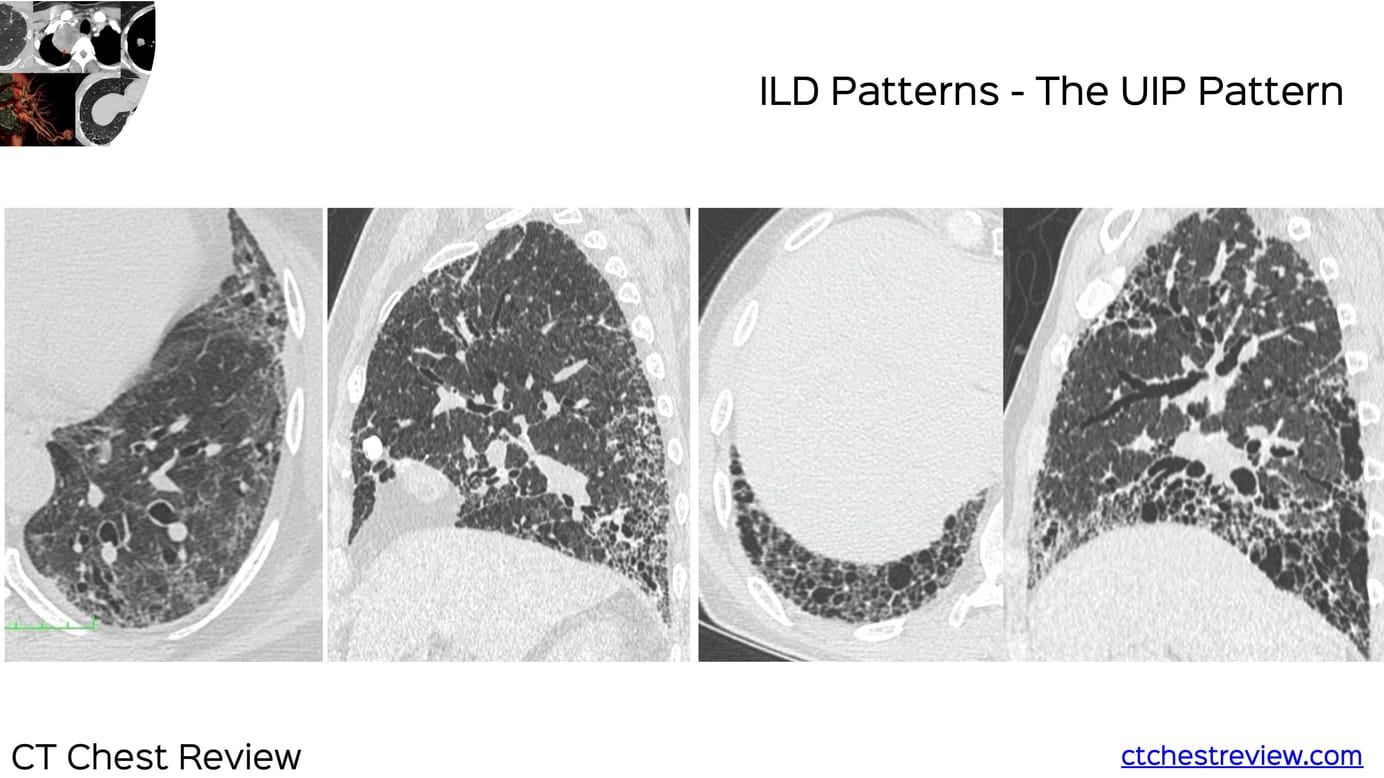

ILD Patterns - The UIP Pattern

The UIP pattern, characterized by reticular opacities, subpleural basal predominance and traction bronchiectasis with or without honeycombing is the classic fibrosing ILD pattern. Primary UIP implies IPF, while secondary UIP implies other etiologies

The first is the usual interstitial pneumonia (UIP) pattern characterized by reticular opacities, subpleural basal predominance and traction bronchiectasis with or without honeycombing. It may be primary or secondary.